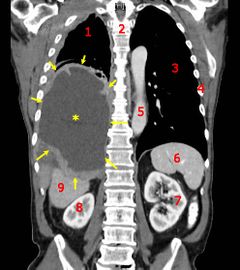

| أشعة مقطعية إكليلية تظهر سرطان كيس الرئة الخبيث. المفتاح: → ورم ←, ★ انصباب جنبي مركزي، 1&3 الرئتان، 2 العمود الفقري، 4 الضلوع، 5 الأورطى، 6 الطحال, 7&8 الكليتان، 9 الكبد. | |